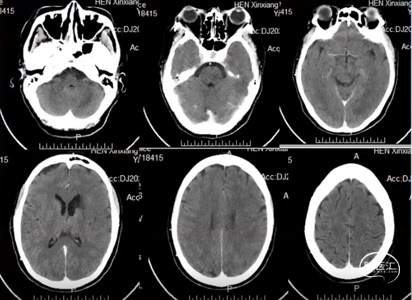

术后24h复查头CT

术后第3天复查头DWI

DWI上左侧基底节区、题枕额顶叶、双侧侧脑室周围高信号为新发病变。

查头SWI

SWI:左侧基底节区、后纵裂左侧脑沟内可见条状低信号影1.后纵裂左侧蛛网膜下腔出血。